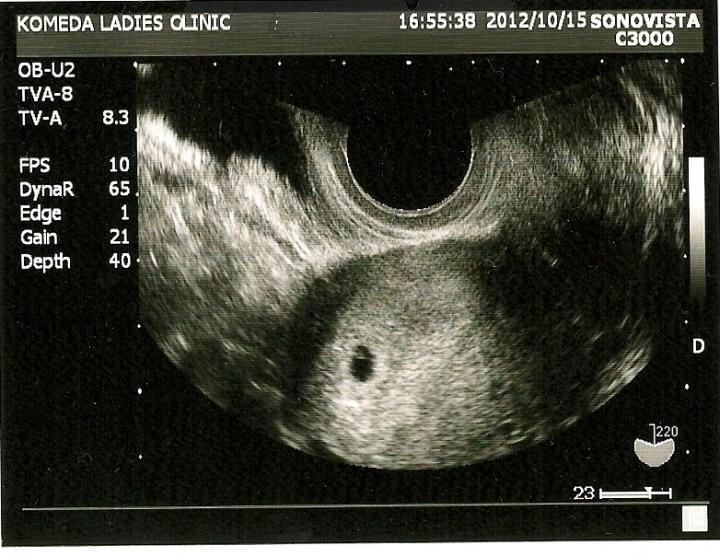

ところで、先日発覚した 私の妊娠ですが・・・

5週目だとのことです(^^9

今は一番安静時期との(^^)